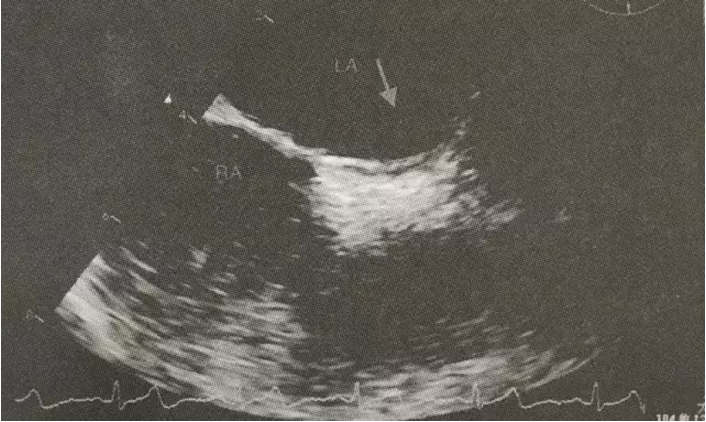

患者为中年女性,反复发生脑梗死,曾就诊于多家医院,考虑过多种临床诊断,包括:(1)患者为中年女性,有高血压病史,反复以脑血管系统受累症状就诊,但短期内既有前循环受累(见图1),又有后循环受累(见图2)的临床表现,且脑血管影像学评估包括超声以及脑血管造影均未见明显为异常。因此不支持脑血管本身病变所致。(2)低血糖症。在外院进行了延时OGTT试验,未发现明显低血糖,同时也进行了自身免疫性因素导致低血糖的筛查,无阳性发现,并且患者发作时表现为非经典低血糖症状(经典的Whipple)三联征:即低血糖症状、发作时血糖降低和供糖后症状迅速缓解),未补充糖症状也可以好转,排除了此种可能。(3)患者为女性,有系统性红斑狼疮家族史,为除外原发性或继发性抗磷脂综合征,入我院后查了LA-SCT(狼疮抗凝物)1.23升高,ANA 1:100,SSA阳性,虽然患者无明显系统受累表现,不能完全除外干燥综合征。但抗磷脂综合征需要3个月内复查抗磷脂抗体,阳性才能确诊。(4)除此之外,该患者临床发作特点为起病急骤、不同次发作累及脑血管不同部位、临床改善迅速,符合脑栓塞表现。但栓子来源于何处?缺血性脑血管病有20%来源于心源性栓塞。因此考虑有无心源性栓塞的可能。本患者虽有高血压病史,但并未发现有阵发或持续心房颤动。进一步于神经内科进行了TCD发泡试验,结果为阳性,提示存在心内秒或心外右向左分流。为进一步明确分流类型,又进行了经食管超声心动图检查及右心声学造影,结果提示存在卵圆孔未闭,且有右向左分流(左心房可见对比剂显影)(见图3)。因此考虑卵圆孔未闭引发的反常栓塞导致脑栓塞可能性最大。因脑栓塞反复发作,故进行了卵圆孔未闭封堵术(见图4)。术后服用阿司匹林100 mg Qd,氯吡格雷75 mg Qd,阿托伐他汀钙片10 mg Qd,随访半年未再发作脑栓塞症状。且复查狼疮抗凝物、抗磷脂抗体、β2-PGI均阴性,不考虑抗抗磷脂综合征,同时患者既往存在的平卧位低氧消失、劳力性低氧症状也消失(既往登山等活动时氧饱和度可降至92%,现一般登山活动无氧饱和度下降)。

图3. 经食管超声心动图加右心声学造影 右心房(RA)内可见声学对比剂,左心房(LA)内可见少量声学对比剂(箭头所指)